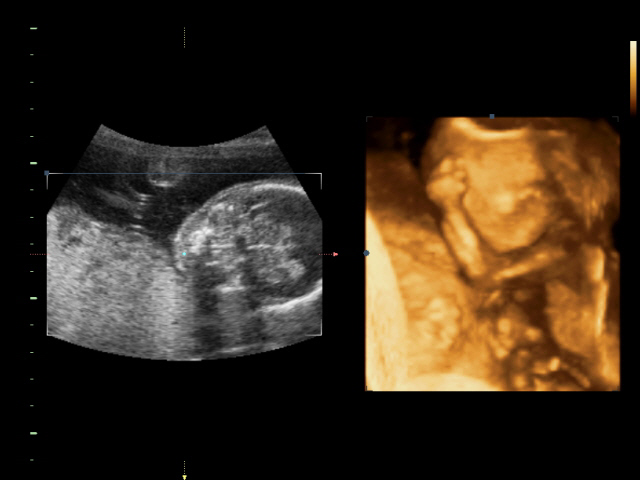

УЗИ, КТГ, доплерМаааальчик)))))

Вчера были на 4д узи... Очень понравилось))0 были всем семейством) Соня наш спал и еле показал кто он)))) как меня только не крутили-вертели... чтоб разбудить его)))) а он дрыхнет и все)))) сначала мосечку свою кулачками прикрывал. потом все таки соезволил нам показать свои губешки и курносый нос))) что-то там ротик открывал)))

Все размеры нашего крохи соответствую сроку. Только пуз больше)))) накушался -толстячок))) Весим 242 гр. сердцебиение 148 уд.мин.

вот так он прятался от нас)))